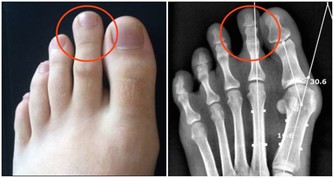

為什麼會從大腳趾頭開始痛,後期還會出現關節畸形?

其實這也是腎虛的一種症狀,因為腎的過濾功能減弱了,血液裡的酸毒排不出去,隨著血液循環流動。大腳趾關節是人體的最末梢關節,酸毒的結晶體最容易積 聚在這裡,也有的人是大拇指關節痛,都是同樣的道理。如果你不去調整腎臟,恢復它的過濾功能,酸毒結晶長期擠壓關節,最後關節不能正常活動,出現變形了。所以痛風患者不僅要改變飲食習慣,更關鍵在於恢復腎臟的機能,提高過濾能力,把酸毒排出體外才不會再複發。